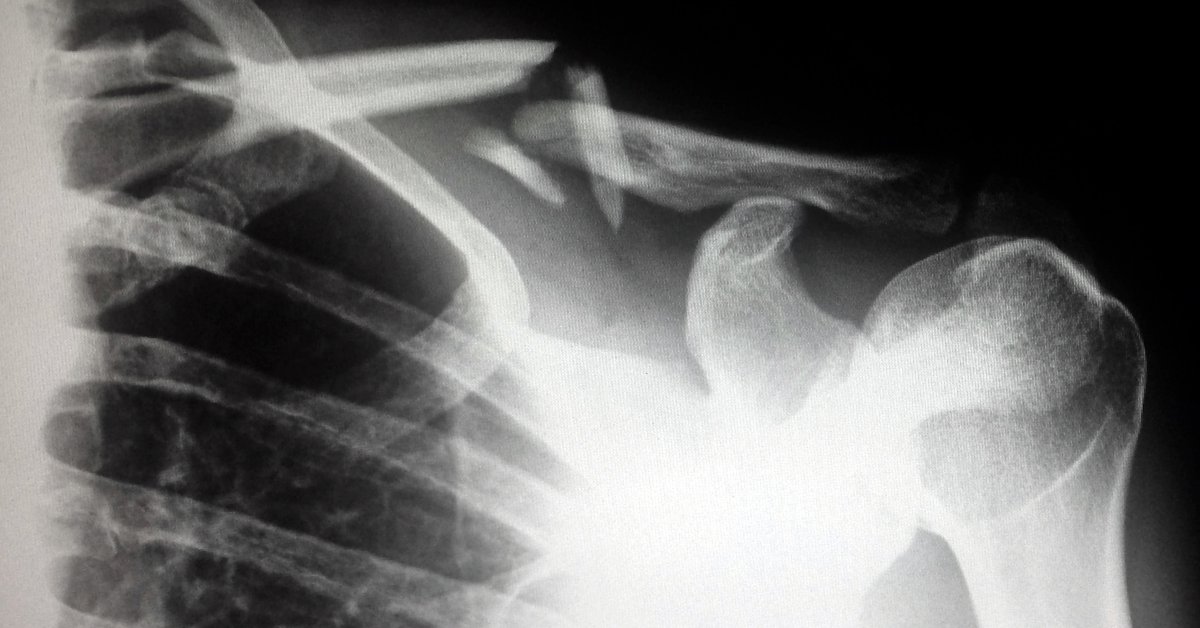

I didn’t see my heel again for three weeks because it was in a cast. However, when my sister took me to a doctor’s appointment to have the cast changed and an x-ray of my femur and heel bone, my heart was in my throat. I was scared. I determined to keep my eyes shut so I would not have the picture of that ugly foot to burden my mind. I wanted to remember my heel as I had last seen it the week before the accident, walking the beaches of Puerto Vallarta, sand-covered, tanned, and perfect.

The whir of the cast cutter buzzed in my ears, but I kept my eyes shut. While heading for the x-ray table, the nurse was holding my leg and moving with me, but my eyes had to remain open in order to maintain balance. And there it was. My heel and ankle, swollen to twice their normal size and bruised badly, repulsed me. There was a spot on the inside of my foot the diameter of a racketball which was black like the skin of an avacado, but oozing. I could not force myself to look at the pin that came out of my heel as it hung over the edge of the x-ray table. How could anything that looked so raw, tender, and misshapen ever heel?